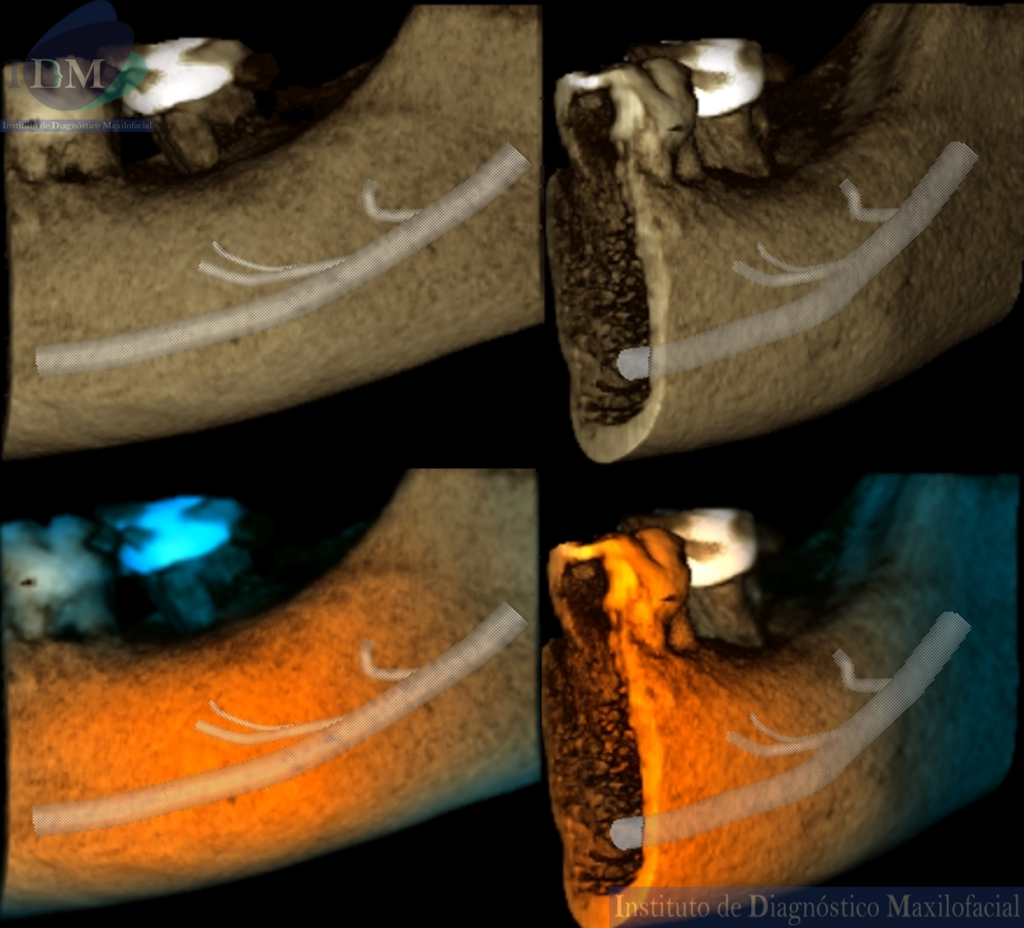

RECONSTRUCCIÓN 3D

Variante anatómica del conducto dentario inferior izquierdo.

La bifurcación del conducto dentario inferior (BCDI) es una variante anatómica del canal mandibular donde anatómicamente se observa dicho conducto dividido en dos ramas, cada una separada en su propio canal por donde discurre una rama neurovascular que puede ser observado en diferentes formas; puede presentarse tanto en un solo lado de la rama mandibular como en ambos lados. Un estudio realizado por el investigador Fukami et al., observaron la presencia de conductos mandibulares bífidos en cadáveres por medio de tomografía computarizada volumétrica y realizó cortes histológicos evidenciando que dichos conductos contenían haces de nervios y arterias de diversos tamaños.

Reconocer la ubicación y configuración del conducto dentario inferior es importante en cualquier tipo de cirugía bucal que implique procedimientos en la mandíbula, tales como la extracción del tercer molar, implante dental y osteotomía sagital de rama. Existen muchos casos de fracaso en el bloqueo del nervio dentario inferior por la presencia del conducto mandibular bífido